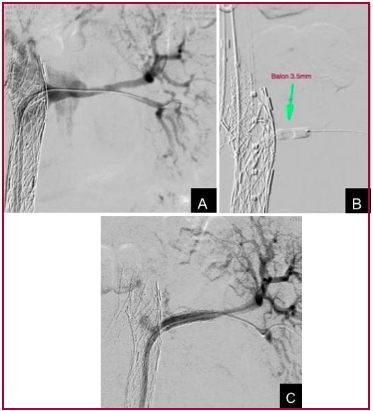

Inmediatamente luego de liberada la endoprótesis fenestrable, se ascendió por vía femoral derecha un catéter guía orientable 8 Fr OSCOR®, que seposicionó en el ostium de la arteria renal izquierda (Fig. 2A). Mediante una guía hidrofílica recta Terumo® 0.035”, se atravesó la membrana de SETA MUG, ingresando en la arteria renal izquierda. Se intercambió por una guía de soporte 0.014”, sobre la cual se colocó primero un balón de angioplastia coronario de 3,5 mm (Fig. 2B) y luego uno de 5 mm de diámetro, con el objetivo de abrir la membrana. A través de este orificio se colocaron dos stents cubiertos de PTFE de 6 mm de diámetro por 22 mm de longitud SIGBI G SETA®, lo que permitió la reconstitución del flujo a través del LV hacia la arteria renal izquierda, cerrando la reentrada en este sector (Fig. 2C).